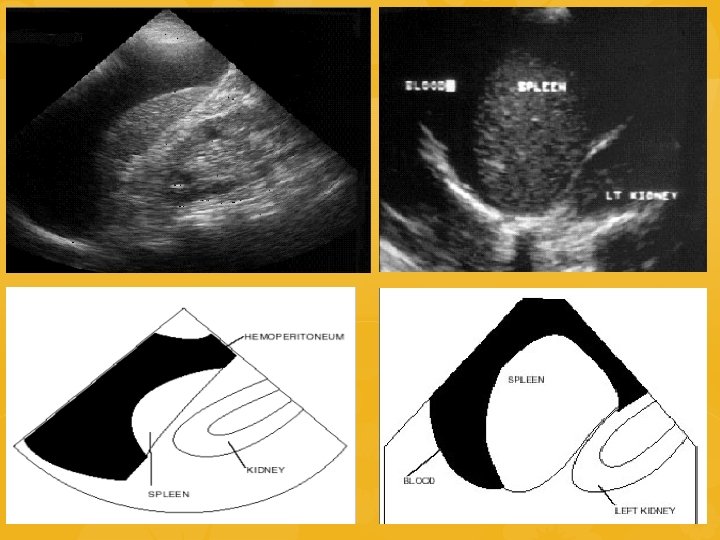

ECOFAST SCOPO: identificare raccolte ematiche nelle cavità del corpo dove non dovrebbe esserci Esplorazione 4 aree 1. QSD 2. Sottoxifoidea 3. QSS 4. Soprapubica INDICAZIONI NEL TRAUMA: • Emorragie toracoaddominali • Trauma penetrante toracoaddominale • Sospetto tamponamento pericardico • Paziente con ipotensione di ndd • Trauma toracoaddominale nella

QSS-Quadrante superiore sinistro • • Sonda parallela alle coste sulla linea ascellare posteriore Insonorizza spazi potenzialmente pieni di liquido presenti tra diaframma e milza e tra milza e rene